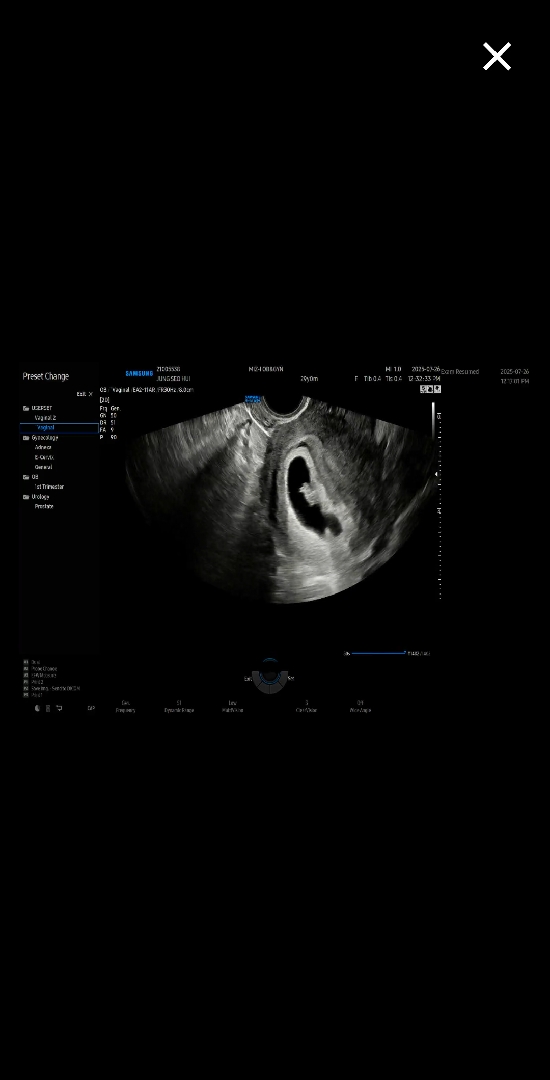

초음파가. 나만 다른가 해서요~~

보통 초음파를 보면 아기가 아래쪽에 보이는데 저 초음파는. 옆에서 붙여있는 느낌이 들어서요~~ 이런경우도 있나요~~병원에서는. 다건강하다고는 하지만. 첫째때랑 달라서 ..의문이 들어서용